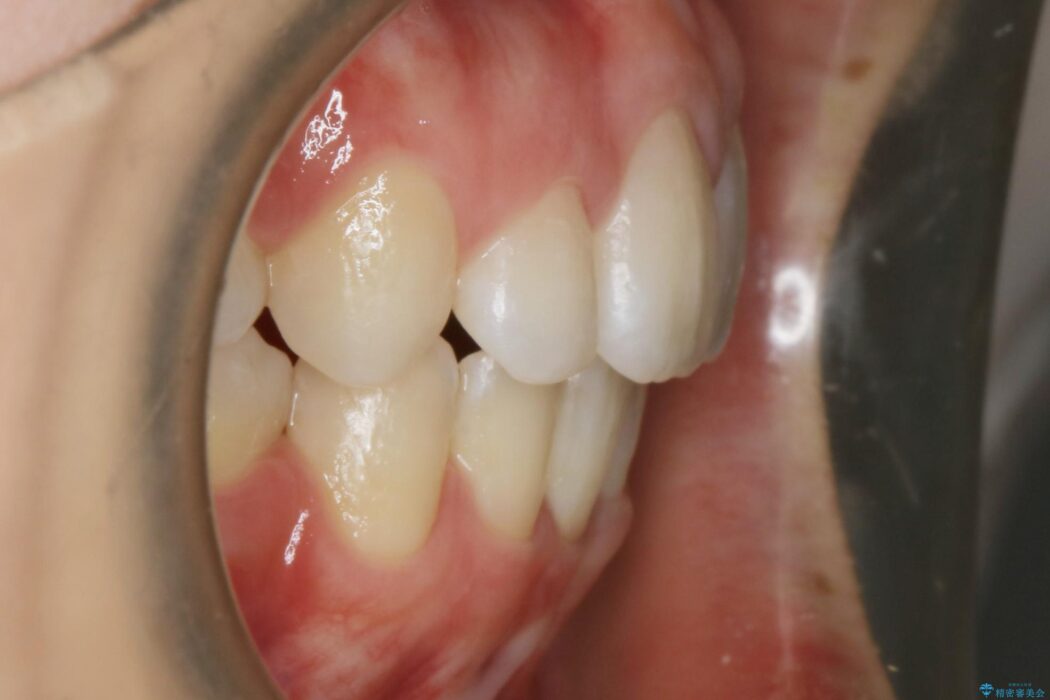

前に出ている口元を下げたいとの主訴で来院されました。

顔貌のビフォーアフターでもわかるように口元の出っ張りが改善され、患者様にはとても喜んでいただけました。

横顔であったり笑った時の印象にも変化があるため、同様のお悩みを抱えている方はぜひご相談ください。